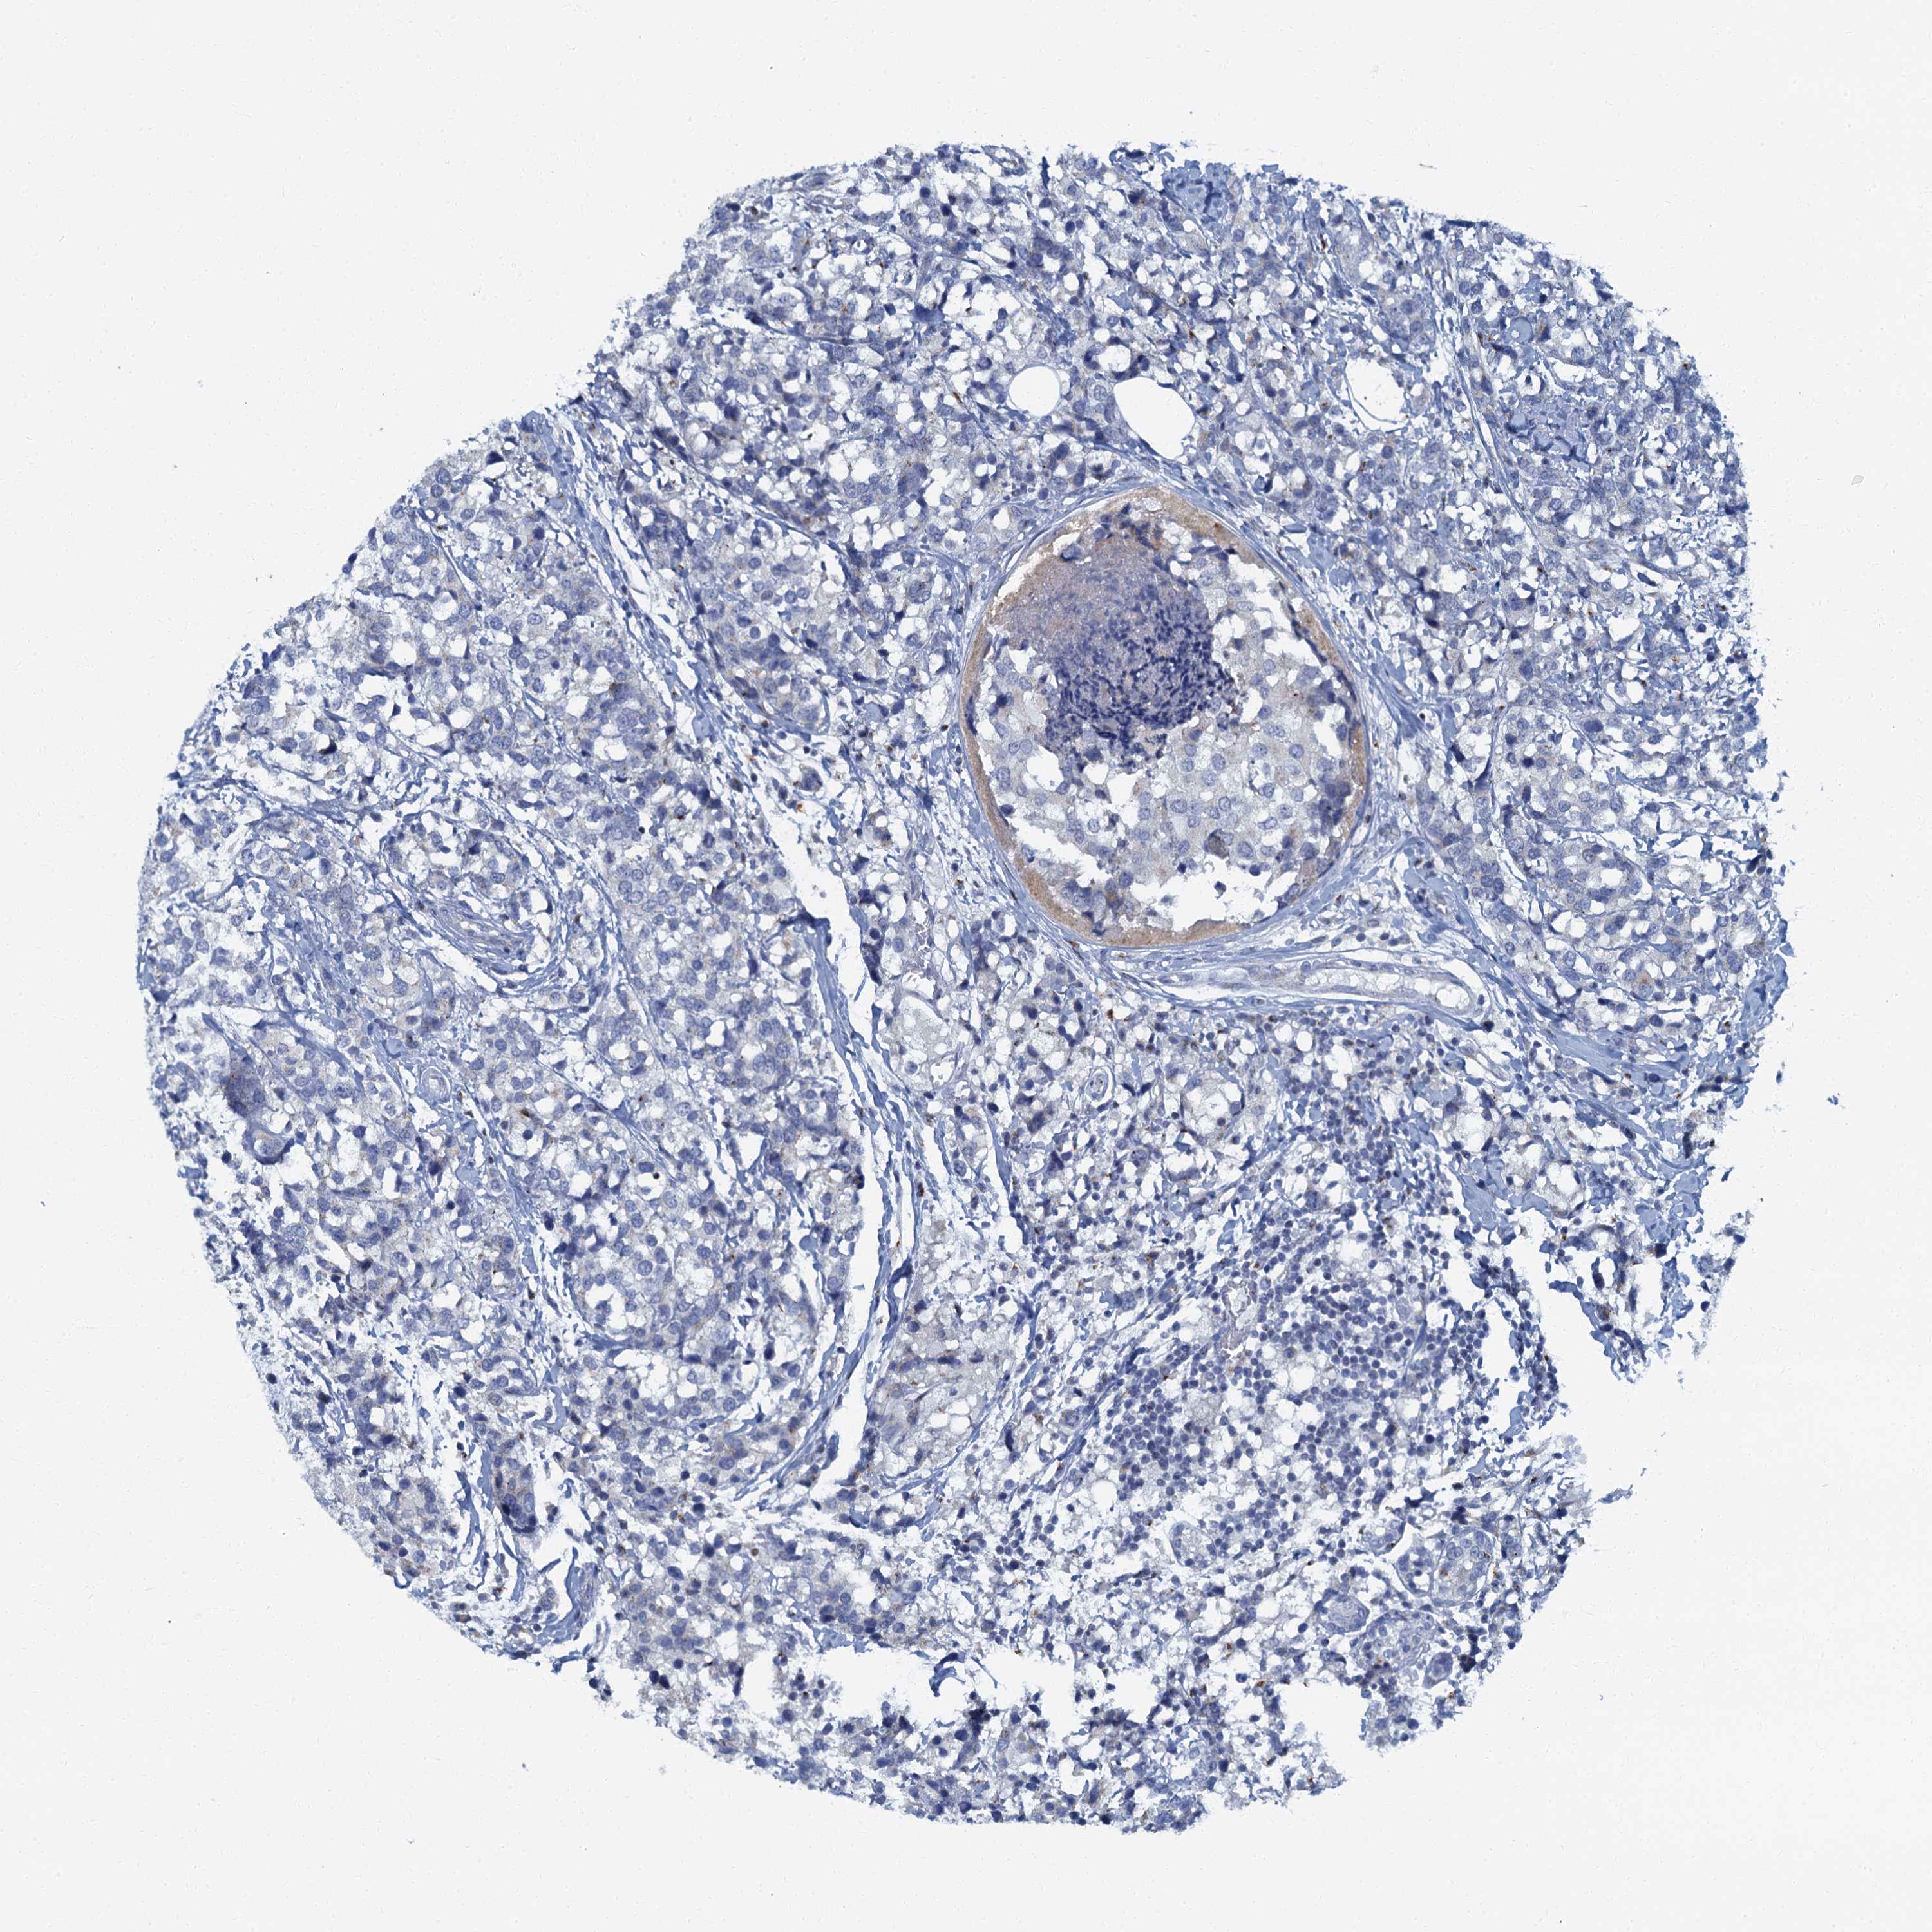

CANCER BREAST CANCER Show tissue menu

Breast cancer

Human cancer